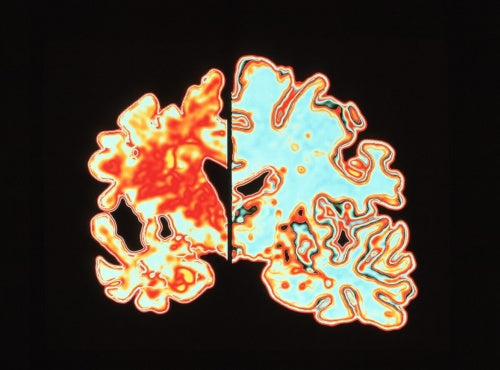

認知症の45%は予防可能、リスクは何歳からでも下げられる

医学誌「ランセット」の認知症に関する委員会が報告書を発表。生涯にわたって認知症リスクを減らすためにできる14の具体的な行動をリストアップ。難聴の人々が補聴器を利用できるようにし、有害な騒音への暴露(ばくろ、さらされること)を減らす。(NATIONAL GEOGRAPHIC記事)